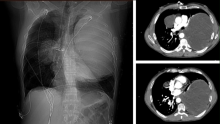

The patient is a forty-five-year-old man with metastatic testicular cancer, who underwent four cycles of chemotherapy with a complete response. Surveillance imaging revealed a 21 x 15 x 12-centimeter mass in the left chest and an 8-centimeter mass in the right upper lobe, consistent with metastasis.

The surgery began with a clamshell incision and vertical sternotomy. Proximal control of the pulmonary artery and superior and inferior pulmonary veins was obtained intrapericardially. A left pneumonectomy was performed.